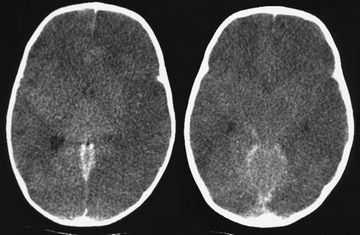

Существует большая точность и разрешающая способность МРТ в диагностике глиом полушарий мозга, этот метод не сопоставим с данными, полученными при КТ-исследовании. Он позволяет более точно определить вид опухоли, степень ее анаплазии и выраженность перифокального отека мозга, что имеет важное значение для выбора наиболее рациональной противоотечной терапии в процессе предоперационной подготовки и планирования хирургического вмешательства (рис. 2,3,4,5,6). На всех рисунках представлены справа результаты МРТ — изображения, а слева — КТ в аналогичных срезах.

Рис. 2 а. КТ. Заметно смещение срединных структур (стрелка). Отек не виден

Рис. 2б. МРТ. Хорошо виден перифокальный отек

Рис. 3а. КТ. Заметно смещение срединных структур (стрелка). Отек не виден

Рис. 3б. МРТ. Хорошо виден перифокальный отек